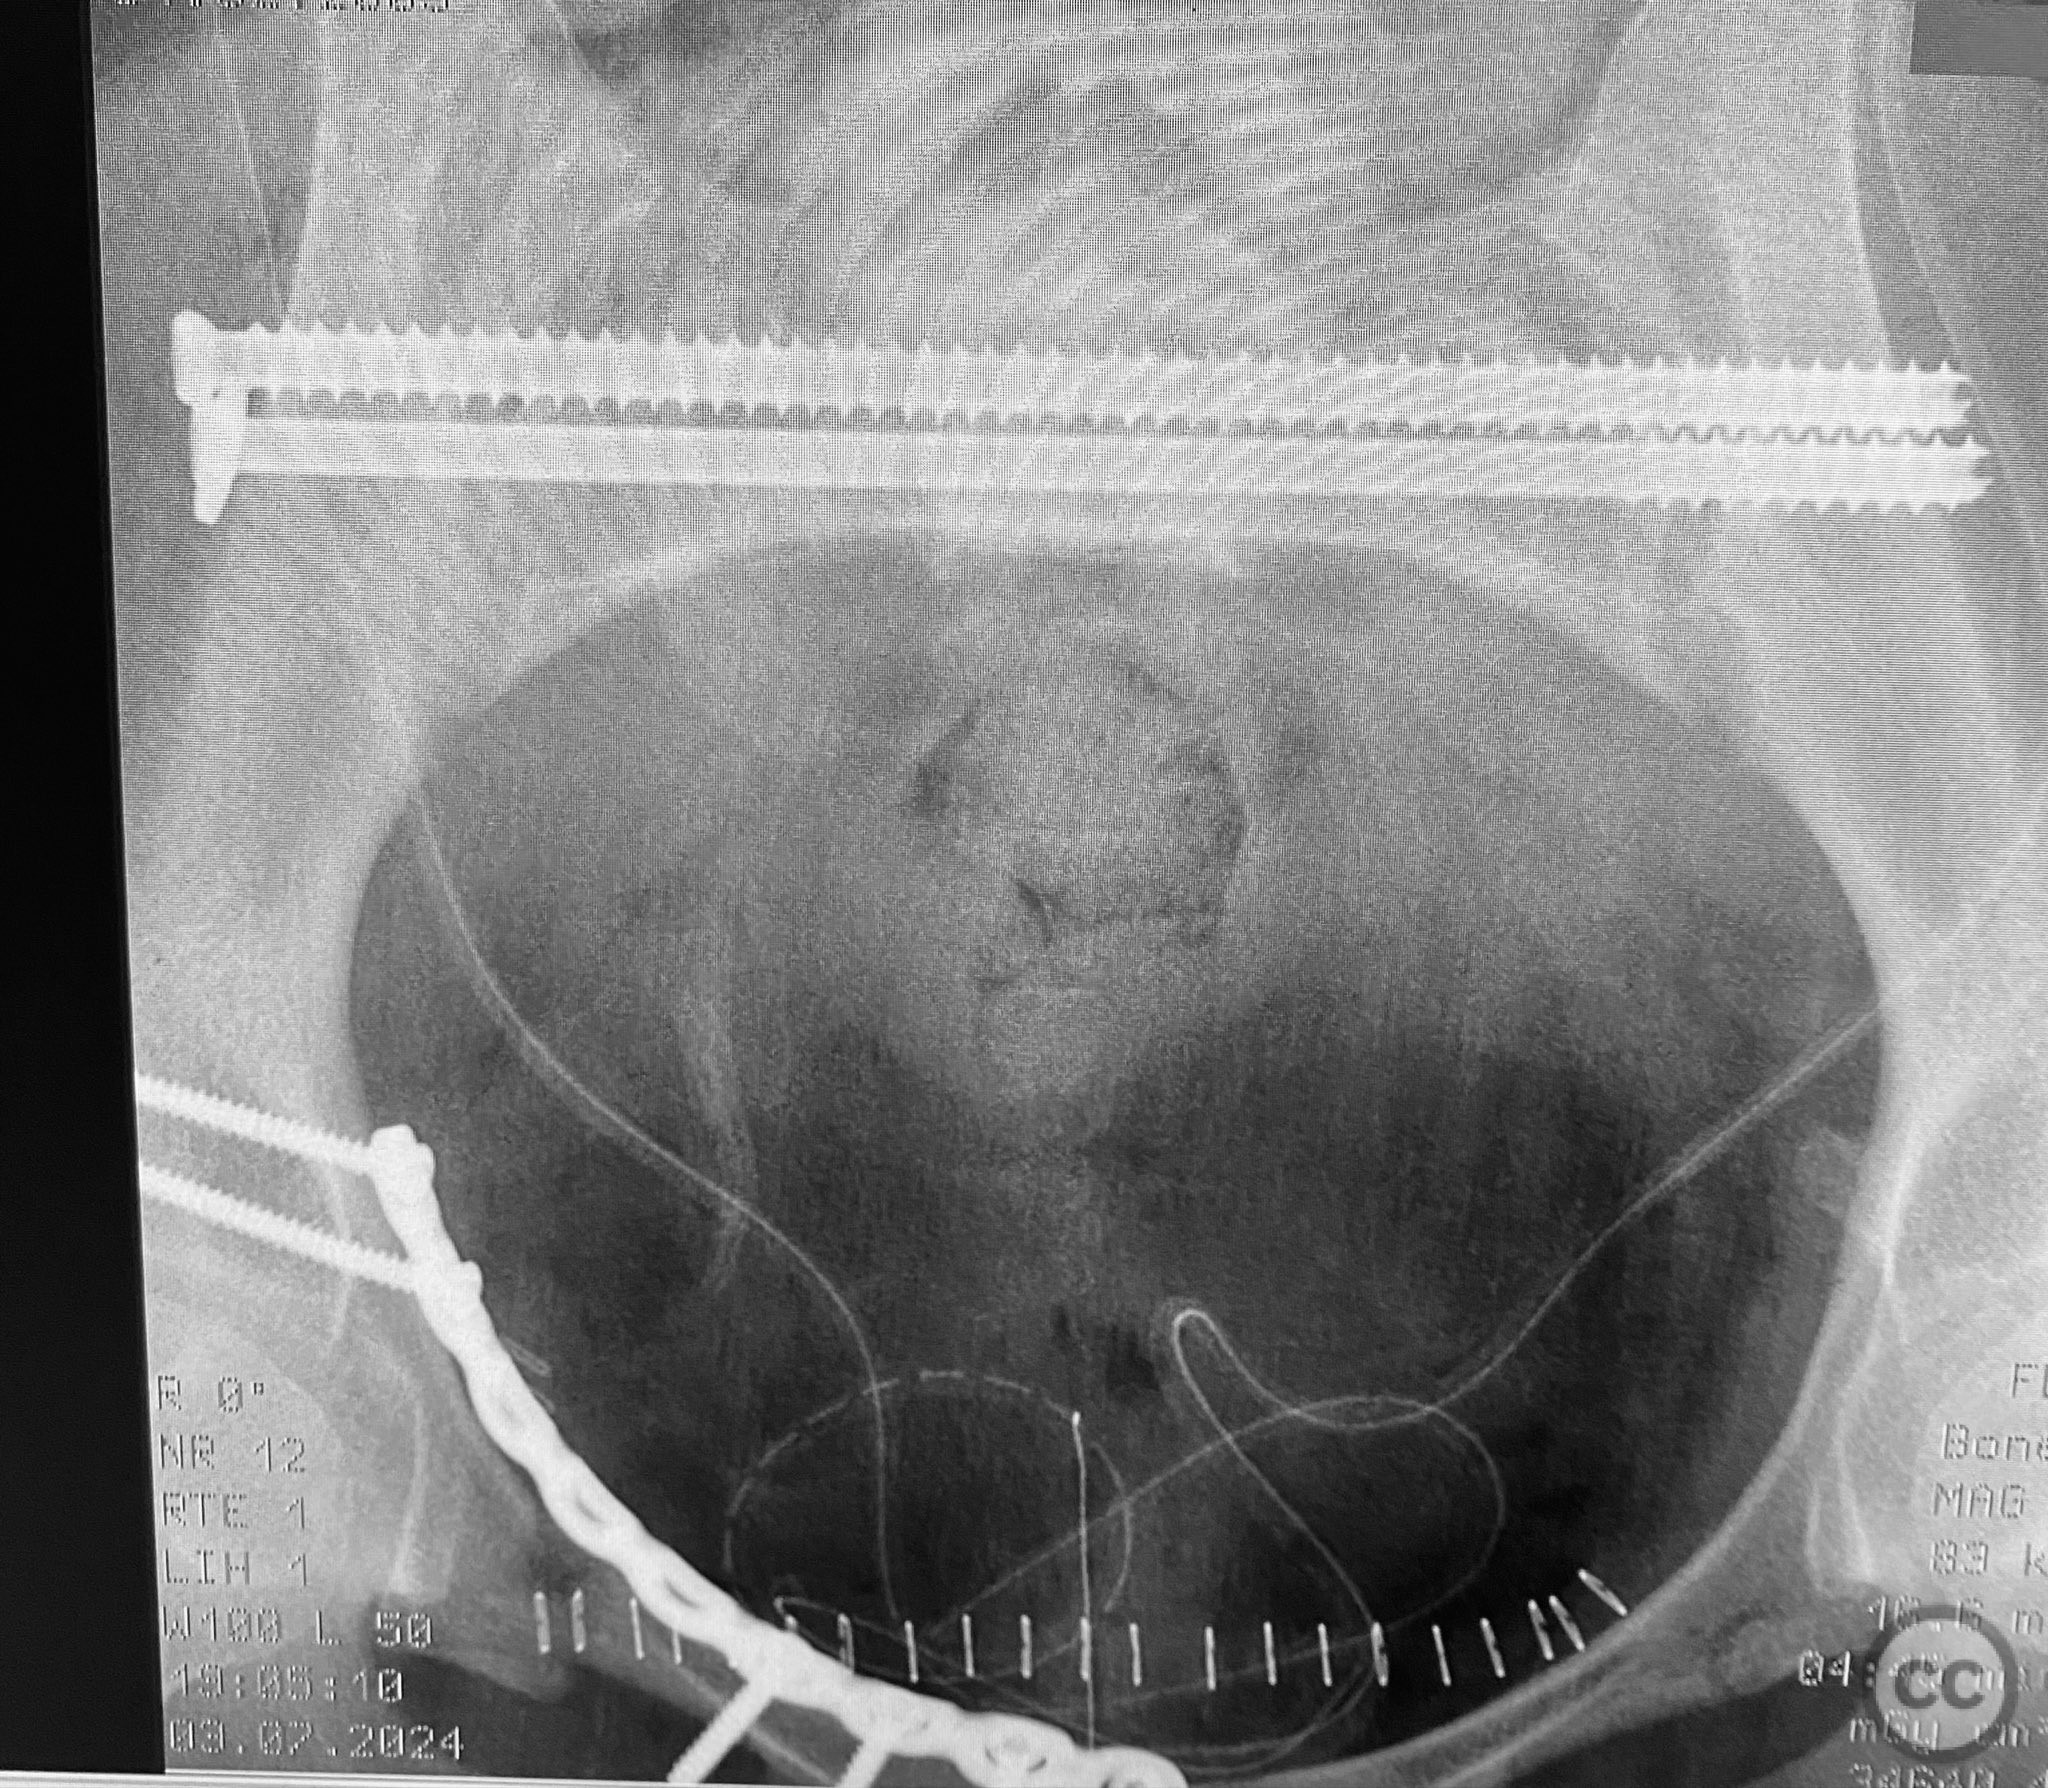

Clinical and radiological findings:  A young adult female sustained a high-energy pelvic injury following a motorcycle crash. She was hemodynamically stable on presentation, with normal neurovascular examination and no evidence of genitourinary, vaginal, or rectal injury. She reported pain localized to both anterior and posterior pelvic regions. Initial plain radiographs (with and without pelvic binder) demonstrated multiple anterior ring fractures and dislocations. The binder images obscured the full extent of injury. Further intraoperative fluoroscopic imaging (AP, inlet, and with lower extremities in "lotus" position) revealed bilateral sacroiliac (SI) joint disruptions (right greater than left), bilateral superior/inferior pubic ramus fractures (right greater than left), and symphyseal diastasis. Notably, the right pubic ramus demonstrated excessive curvature, complicating potential percutaneous screw fixation. AO/OTA classification: 61-C1.3 (bilateral complete disruption of the posterior arch with associated anterior ring injury). Young-Burgess classification: APC III.

Patient positioning:  The patient was positioned supine on a radiolucent operating table under general anesthesia. For intraoperative assessment, the lower extremities were placed in a "lotus" position to enhance visualization of pelvic ring injuries under fluoroscopy.

Intraoperative fluoroscopy with AP and inlet views, as well as dynamic positioning of the lower extremities, was critical in fully delineating the extent of injury, which had been underestimated on preoperative imaging due to binder application. The excessively curved morphology of the right pubic ramus precluded safe or effective straight screw fixation; therefore, ORIF with a contoured plate was performed using intrapelvic exposure for optimal fit and stability. Indirect closed reduction of the SI joints was accepted, followed by percutaneous trans-sacral screw fixation under fluoroscopic guidance. This case highlights the necessity of thorough intraoperative assessment for occult or underestimated injury patterns in complex pelvic trauma, particularly when initial imaging is performed with a pelvic binder in situ.